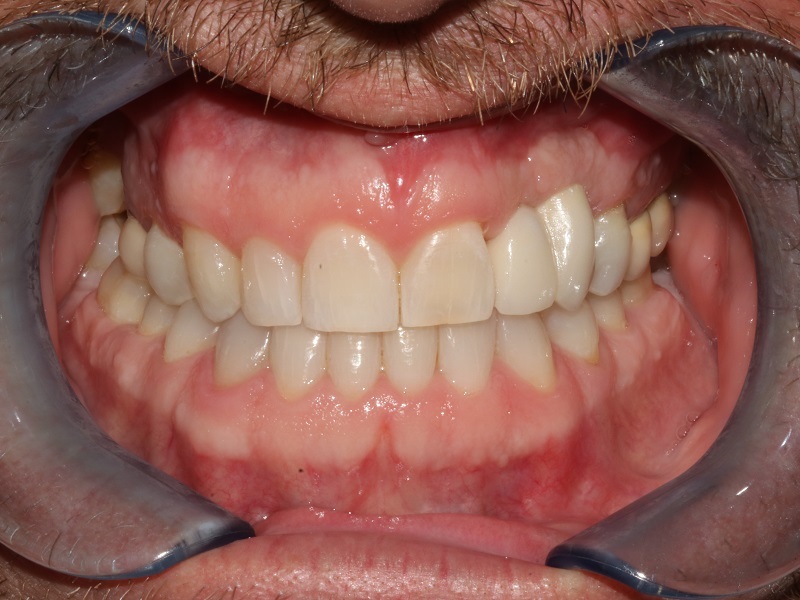

WE'RE HERE TO GIVE YOU A Great SMILE

JUST LIKE WE HAVE FOR ALL OUR OTHER WONDERFUL PATIENTS!

Revitalize Your Smile

Transform your smile with dental implants that look and feel like natural teeth. Enjoy the confidence that comes with a freshly restored smile.